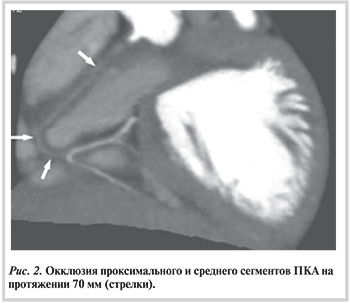

При динамическом наблюдении тромбы регрессировали в 5 аневризмах у 4 больных без тромболизиса на фоне применения стандартной антитромботической терапии: гепарин, низкомолекулярные гепарины, варфарин, ацетилсалициловая кислота (АСК). У 2 пациентов развилась окклюзия правой КА. У одного из них мы не выявили клинических и инструментальных признаков ишемии миокарда, при МСКТ дистальный сегмент правой КА и задняя нисходящая артерия заполнялись контрастным веществом из системы ЛКА по артерии Кюгеля, обнаруживались признаки реканализации (рис. 2).